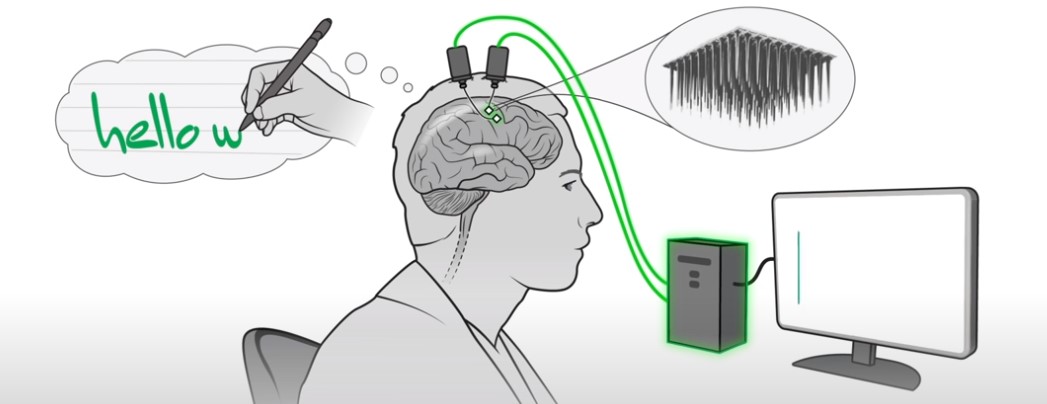

Τεχνητή νοημοσύνη μετατρέπει σε κείμενο τη σκέψη [Βίντεο]

Επιστήμονες στις ΗΠΑ δημιούργησαν το πρώτο «έξυπνο» – εμφυτευμένο στον εγκέφαλο – σύστημα που μετατρέπει, σε πραγματικό χρόνο, σε κείμενο στην οθόνη ενός υπολογιστή το γράψιμο με το χέρι που φαντάζεται με τον νου του ένας παράλυτος. Αυτή η καινοτομική διεπαφή εγκεφάλου-υπολογιστή (Brain-Computer Interface-BCI), εφόσον βελτιωθεί περαιτέρω, θα επιτρέψει σε παράλυτους ανθρώπους να «γράφουν» γρήγορα […]